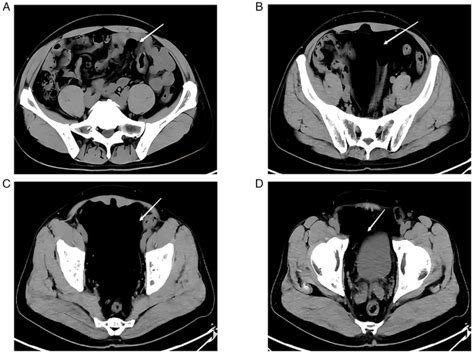

• space of retzius radiology

• space of retzius hemorrhage

• space of retzius hematoma